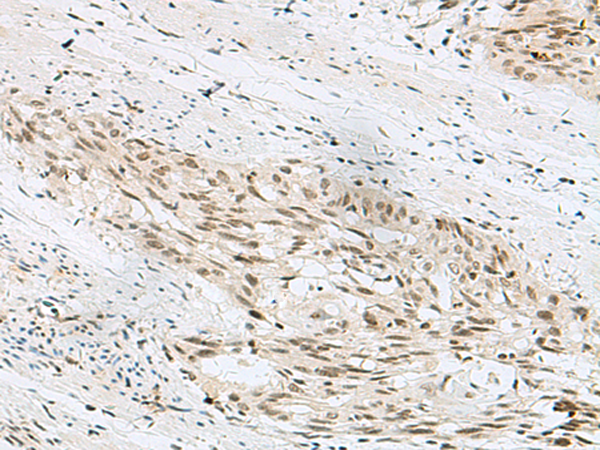

分类: 科研抗体货号: P13569别名: HEXO; THEX1; 3'HEXO应用: IHC反应种属: Human, Mouse, Rat